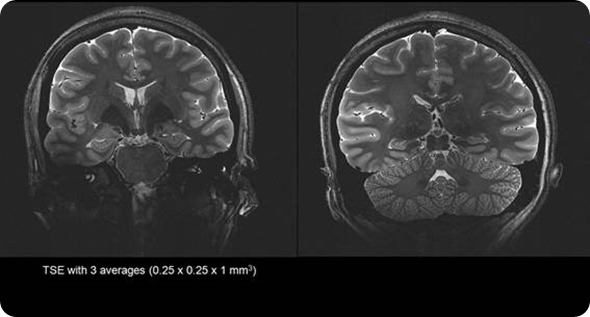

Stronger magnet fields increase the signal-to-noise ratio of the MRI signal. This increase in signal to noise can then be used to increase the spatial or temporal resolution of the image. Simply put, the higher the magnetic field strength, the more detail we can see inside the body.

Most MRI scanners operate between 1.5 Tesla and 3 Tesla. Due to benefits of the increased resolution at higher filed strengths SMT have developed a ground breaking 7 Tesla system, the MAGNETOM Terra. This new system has been designed to meet the demands of both researchers and clinicians.

Due to the extra signal to noise available at 7 Tesla we are able to generate exquisite image quality to show vascularity of the brain without the need for an injection of contrast media often required at lower field strengths.

This allows researchers to identify lesions and bleeds more easily, and the specific areas of the body affected - potentially enabling unprecedented insights into hard-to-diagnose conditions.